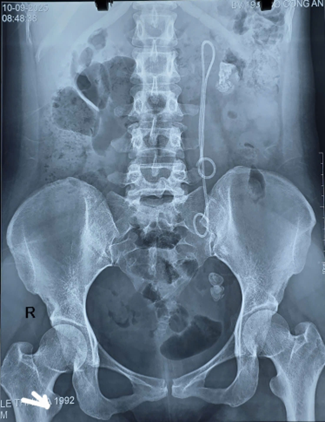

Qua thăm khám lâm sàng và cận lâm sàng, bệnh nhân được chẩn đoán: Sỏi thận trái, sỏi niệu quản trái đoạn 1/3 dưới, còn Sonde JJ trái đặt 15 năm chưa rút.

Trường hợp này, do Sonde JJ tồn tại tới 15 năm, bệnh nhân xuất hiện sỏi to ở nhiều vị trí, Sonde bám sỏi và di chuyển bất thường, khiến quá trình điều trị phức tạp và tiềm ẩn nhiều nguy cơ.